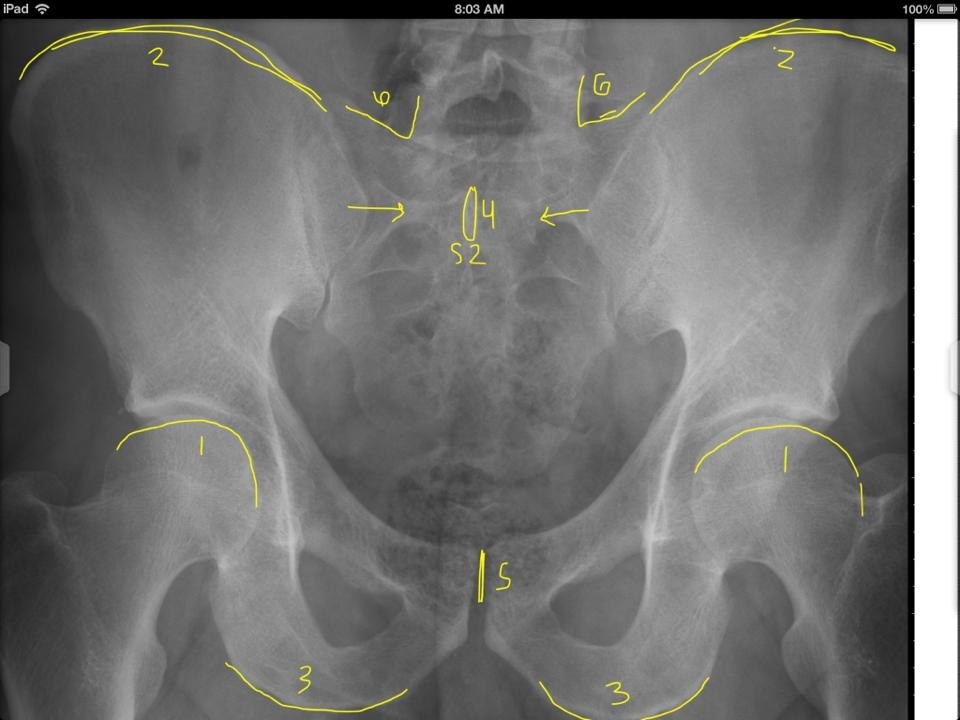

14

1

A

Occipital Condyle

(anterior/posterior)

15

2

Anterior Tubercle C1

16

3

Posterior Arch C1

17

4

Odontoid Process C2

18

5

Atlanto-Dental Interspace